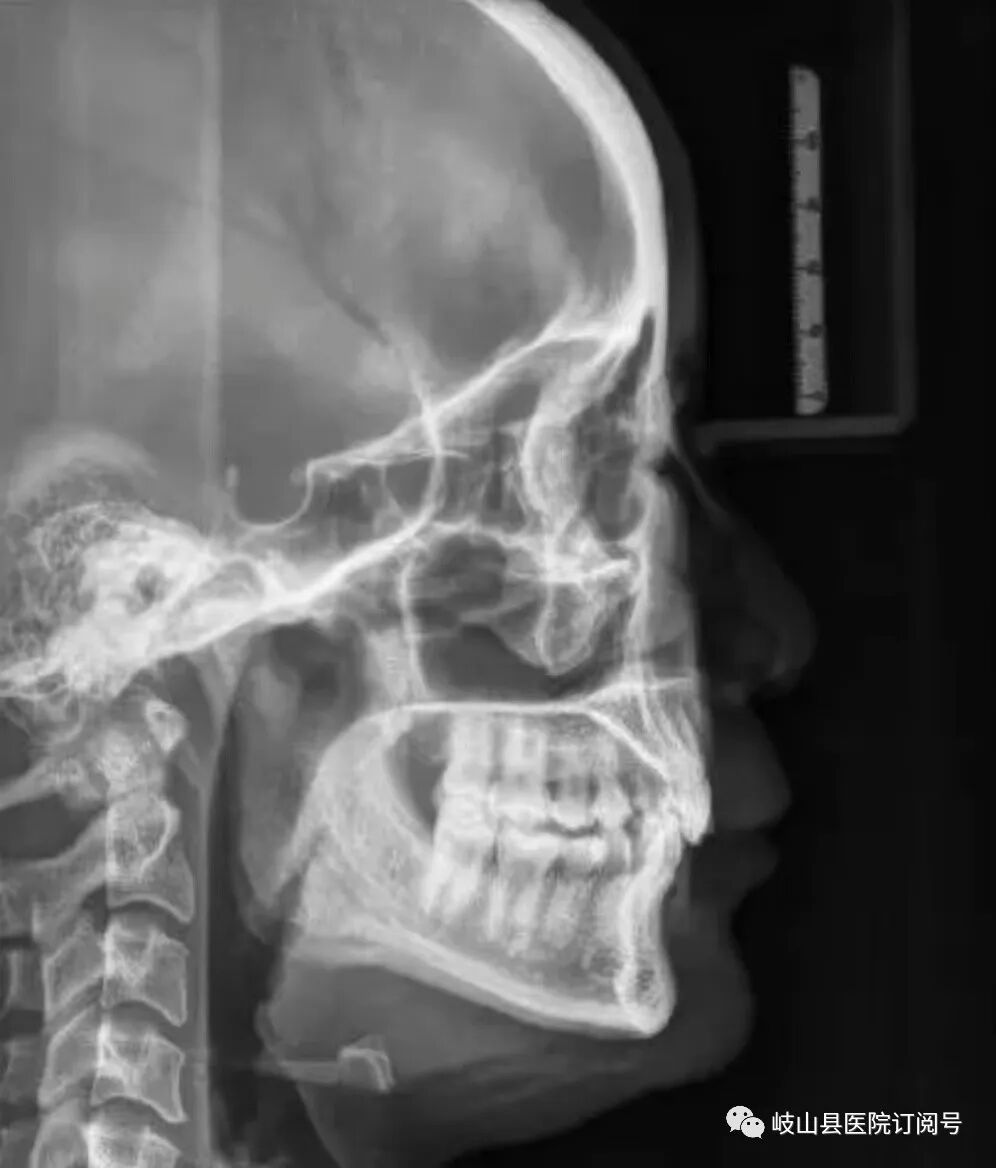

为了更好的为岐山人民服务,提高自身科室的诊疗水平和质量,县医院在原有的基础上引进了卡瓦X-TREND口腔三合一CBCT现代化数字检查设备,现已投入使用。该设备的引进,能给医生的诊断和治疗过程带来便利,能为更多的患者带来全面细致的治疗体验,提供更先进、更高效的口腔诊疗服务,提升岐山县医院口腔科的整体实力和诊疗水平。‍

卡瓦CBCT即卡瓦口腔颌面锥形束CT(cone beam computed tomography),其基本原理是X线发生器以较低的射线量(通常球管电流在10毫安左右)围绕投照体做环形数字式投照,然后将围绕投照体多次数字投照后“交集”中所获得的数据在计算机中“重组”,进而获得高清三维图像。卡瓦X-TREND“三合一”CBCT即具有口腔曲面断层片、头颅侧位定位片和多功能CT三种拍摄功能,满足了口腔临床诊断的所有需要。

是目前国际最先进的口腔专用CT,在业界被誉为神奇的“慧眼”,具有扫描快、范围大、精度高、应用广、放射量极低的特点。可以通过其强大的处理软件功能以及面部匹配技术迅速形成清晰逼真的三维图像,较传统CT对于牙齿及颌骨组织的结构成像质量更好,彻底解决了口内牙片机、口腔全景机等口腔X射线设备影像重叠、畸变的问题,可以便捷直观地发现多种牙齿隐患问题,为口腔医生提供了精准的诊断与治疗依据。

卡瓦CBCT广泛应用于口腔各个领域:口腔颌面外科方面用于肿瘤、囊肿的范围及与上颌窦及下颌神经管的关系,颌骨骨髓炎的诊断,骨折的诊断及术前指导,阻生智齿的诊断及拔除指导,多生牙及埋伏牙的定位及毗邻关系,颞下颌关节病的诊断等;牙体牙髓方面可以清晰观察根管的数目及形态、能够发现变异的细小根管、早期的根尖炎症、牙根折裂等情况;牙周病方面可以确定牙周病的病变程度及指导治疗;牙列错颌畸形矫治方面用于研究颅面生长发育,诊断分析、矫治设计、前后对比,头影测量等;口腔种植方面涵盖了种植牙的每一个种植细节,提供了可靠的理论依据,确保种植牙手术的成功率。(口腔科  陈亚萍)